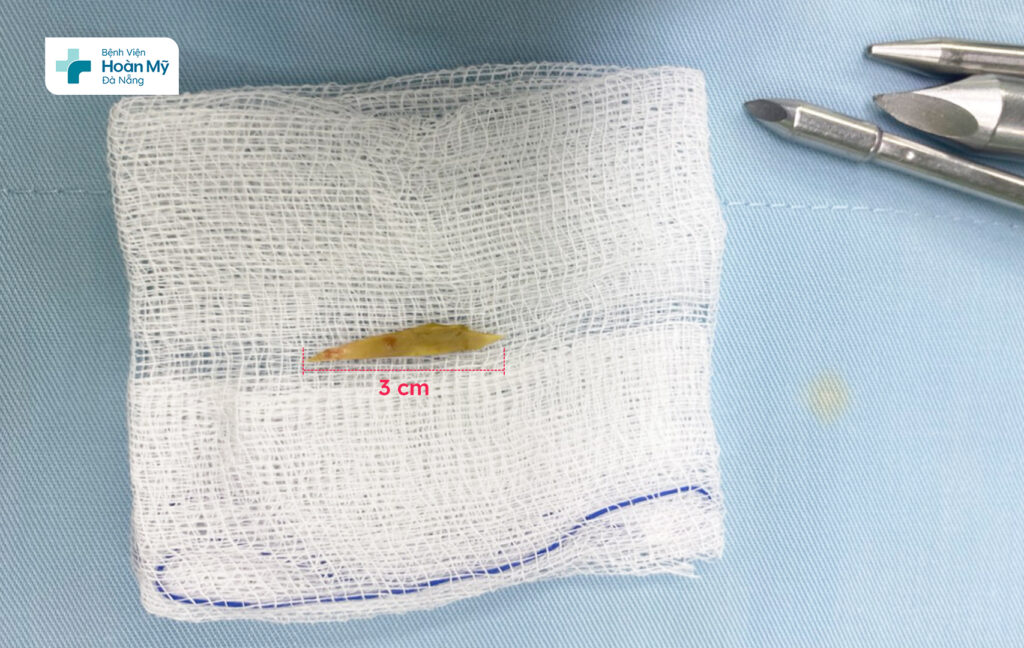

Các bác sĩ Khoa Ngoại Tiêu hóa – Gan – Mật, Bệnh viện Hoàn Mỹ Đà Nẵng đã thực hiện phẫu thuật nội soi cấp cứu gắp thành công dị vật ra khỏi đường tiêu hóa cho người bệnh. Dị vật là mảnh xương gà sắc nhọn, dài khoảng 3cm đâm thủng ruột non của […]

Các bác sĩ Khoa Ngoại Tiêu hóa – Gan – Mật, Bệnh viện Hoàn Mỹ Đà Nẵng đã thực hiện phẫu thuật nội soi cấp cứu gắp thành công dị vật ra khỏi đường tiêu hóa cho người bệnh. Dị vật là mảnh xương gà sắc nhọn, dài khoảng 3cm đâm thủng ruột non của người bệnh.

Trưa 21/7, Khoa Cấp cứu – Bệnh viện Hoàn Mỹ Đà Nẵng tiếp nhận một trường hợp vào viện vì đau bụng nhiều vùng bụng quanh và dưới rốn, khởi phát từ sáng và ngày càng tăng, cơn đau liên tục, không có cơn trội. Tại Khoa Cấp cứu, người bệnh được thăm khám, siêu âm bụng, chụp cắt lớp vi tính ổ bụng và làm một số xét nghiệm máu để chẩn đoán bệnh. Kết quả phát hiện một dị vật bất thường (nghi là mảnh xương) đâm xuyên thành ruột non. Xác định nguy cơ dị vật đâm thủng ruột non có thể gây ra những biến chứng phức tạp, người bệnh được các bác sĩ hội chẩn và chỉ định phẫu thuật nội soi cấp cứu lấy dị vật. Trong quá trình phẫu thuật, các bác sĩ phát hiện dị vật là mảnh xương gà đâm thủng ruột non của người bệnh, gây nên tình trạng viêm phúc mạc. Sau khoảng gần 01 giờ phẫu thuật nội soi can thiệp, ekip đã gặp thành công dị vật đường tiêu hóa cho người bệnh một cách an toàn.

Dị vật là mảnh xương gà được lấy ra từ ruột non của người bệnh